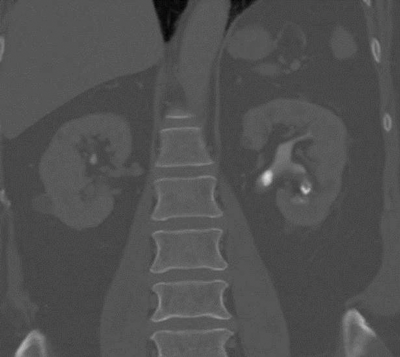

The collecting systems and ureters should be opacified on the excretory phase of CT urogram and adequate distension and opacification of the ureter and pelvicalyceal system are vital when evaluating the urothelium. Filling defects can be difficult to appreciate on abdominal windows and subtle filling defects are more clearly seen on bone window settings. This can allow ureteric neoplasms to be distinguished from other causes of filling defects. Figure 4 shows an example of a filling defect in the left ureter that is more clearly defined on bone windows compared with abdominal windows. This was a female patient who presented with cyclic pain and was found on biopsy to have endometriosis in the left ureter.

Figure 4a: Abdominal windows filling defect.

Figure 4b: Bone windows filling defect.